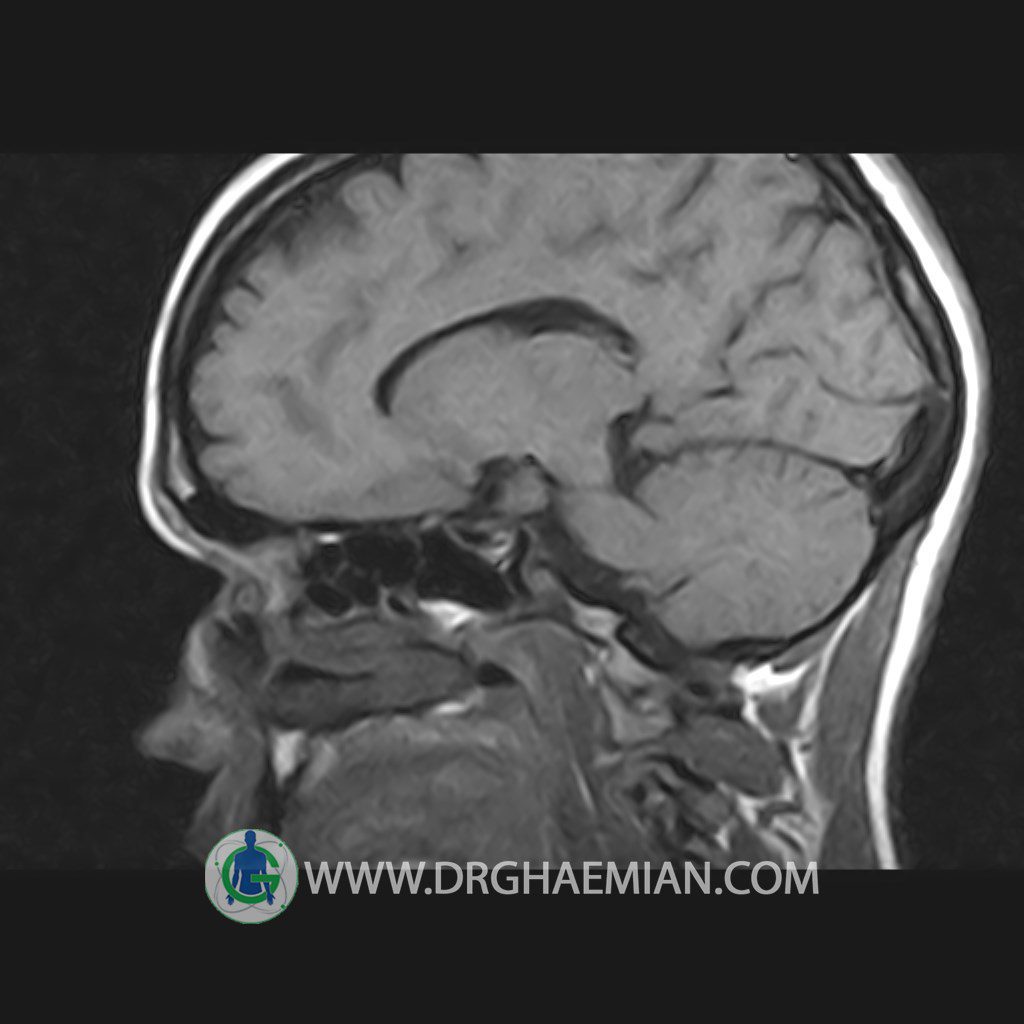

پزشکان اغلب از تصویربرداری ام آر آی برای تشخیص و درمان عارضه های پزشکی که فقط با استفاده از اشعه ایکس یا میدان مغناطیسی و امواج رادیویی قابل مشاهده است، استفاده می کنند. دستگاه ام آر آی تصاویر دقیق از ساختار های داخلی بدن ایجاد می کند. در این کیس هیپرپلازی هیپوفیز و آدنوم مشاهده می شود.

HYPOPHYSIS MRI

(with and without contrast)

Technique: Axial , coronal T1 , Axial , coronal , sagittal T2 , Axial, coronal T1 post Gd & 64 dynamic thin coronal slices.

REPORT :

The sella shows normal size , position and configuration .

The borders of its floor and walls are smooth and sharply defined .

The infundibulum is centered and of normal size .

The optic chiasm and suprasellar spaces appear normal .

The cavernous sinus and imaged portions of the internal carotid artery and carotid siphon are unremarkable .

Evaluable portions of the neurocranium show no abnormalities .

The sphenoid sinus is clear and pneumatized .

– Mild convexity at superior border of pituitary gland with post contrast homogeneous enhancement suggestive for pituitary hyperplasia & iso signal adenoma

is seen